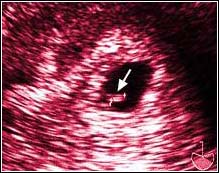

Week Sixteen. The fetus is now six inches long. During

this examination we saw the two hemispheres of a brain,

delicate ears barely protruding from the sides of a head,

a spinal cord like two winding rows of kernels on an ear of corn, and,

as can be seen in this picture, the individual bones of a hand.